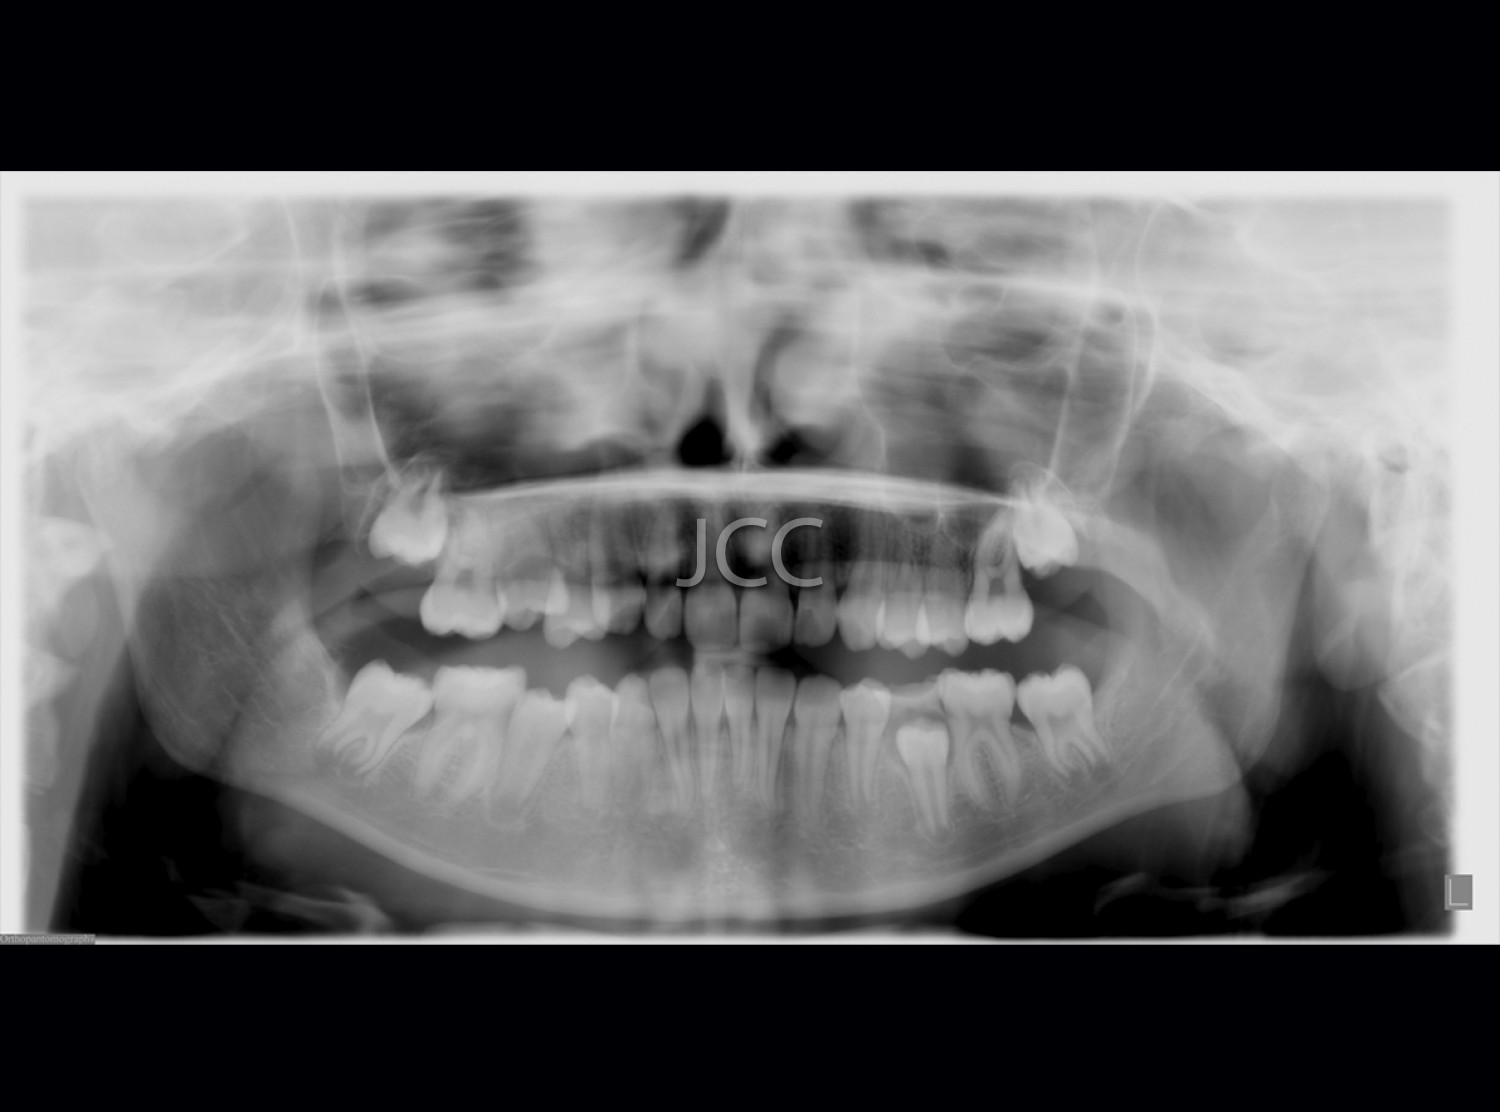

Dental Radiology - Orthopantomography

Orthopantomography is an extraoral radiographic examination, essential in dental medicine, which makes it possible to collect information about the inferior segment of the face, below the orbits.